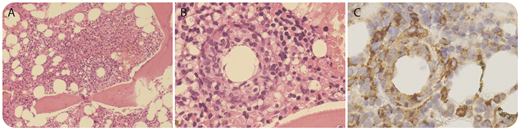

A 53-year-old woman presented with fever, chills, and rigors associated with occipital headache with no localizing sign or symptoms. She had recently returned to Australia after spending 2 months in Cambodia. C-reactive protein level peaked at 120 mg/L. Initial extensive microbe cultures were negative. A whole-body computed tomography scan did not detect any infection or malignancy. As part of the work-up for fever of unknown origin, a bone marrow biopsy was performed. Her bone marrow aspirate was hypercellular with increased granulopoiesis that was left shifted. Careful examination of the trephine sample showed occasional noncaseating ring-shaped granulomas (panel A, original magnification ×10; panel B, original magnification ×40; hematoxylin and eosin stain). Monocytes and histiocytes were diffusely increased and surrounded the granulomas (panel C, original magnification ×40; CD68 immunohistochemical stain). A sample with Ziehl-Neelsen stain was negative and there was no malignant infiltration. Although epithelioid/ring granulomas are characteristic of Q fever, they are not pathognomonic of Q fever and have been reported in patients with viral infections, brucellosis, leishmaniasis, and lymphomas. Q fever serology demonstrated seroconversion consistent with recent infection.